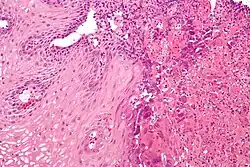

Microscopic Slide of Infectious Esophagitis

Microscopic Slide of Eosinophilic Esophagitis